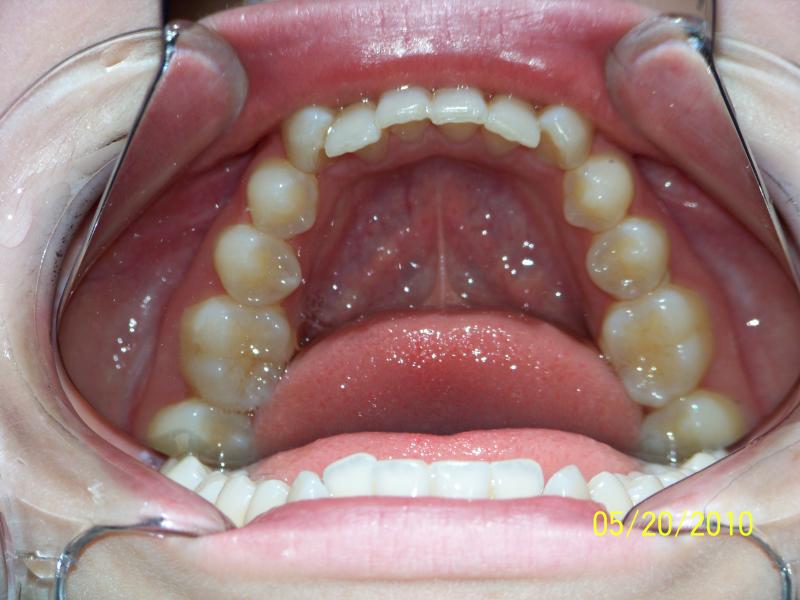

Isabelle G.

Invisalign Case

INVISALIGN, 10 months, 1 series of aligners to correct alignment, deep overbite and shift teeth to the right to match upper and lower mid line, TOTAL TREATMENT TIME: 10 months COSMETIC DENTISTRY: incisal reduction of anterior teeth before and after Invisalign.

Deep Overbite, Teeth Reshaping, Testimonial